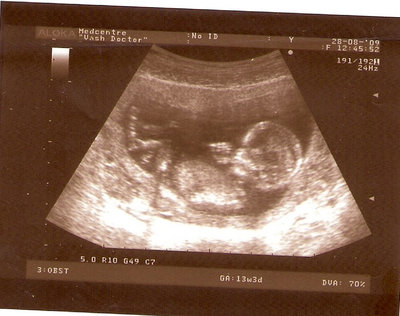

13 НЕД И 5 ДНЕЙ

| Вложения: |

3.jpg [ 96.81 КБ | Просмотров: 2445 ]

Nikisa писал(а): Foto prosto chudesnoe. A na kakom sroke uznali, chto sin.............. НА 13 НЕДЕЛЯХ.КАК РАЗ ВОТ В ЭТО узи, ОНО УМЕНЯ ВТОРОЕ БЫЛО. ЭТО КОНЕЧНО МАЛЕНЬКИЙ СРОК ДЛЯ ОПРЕДЕЛЕНИЯ ПОЛА. НО Я ПОПРОСИЛА ВРАЧА(ЭТО КТСТАТИВ РОССИИ БЫЛО) ХОТЯ БЫ ПРЕДПОЛОЖИТЬ. ЕЙ ВСЁ ТАКИ УДАЛОСЬ РАССМОТРЕТЬ.НУ ВООБЩЕМ ЧЕРЕЗ НЕСКОЛЬ ДНЕЙ ПОЙДУ К ВРАЧУ, УЖЕ АМЕРЕКАНСКОМУ И УЗНАЮ ТОЧНО. К ТОМУ ВРЕМЕНИ У МЕНЯ БУДЕТ СРОК 18 НЕДЕЛЬ. ХОТЕЛОСЬ БЫ ПОСМОТРЕТЬ НА ДРУГИЕ ФОТО НА ЭТОМ СРОКЕ ИЛИ БОЛЬШЕ. ТАК ЧТО ВЫКЛАДЫВАЙТЕ, ЕСЛИ НЕ ЖАЛКО!